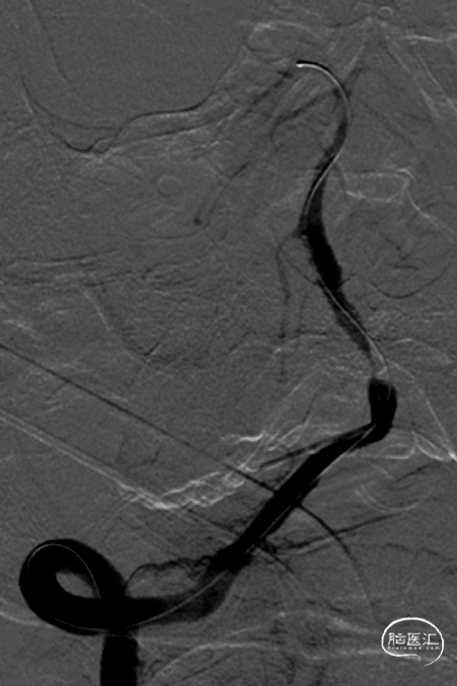

气管插管全麻。6F 指引导管、5F多功能管、泥鳅导丝同轴,将指引管放置于右侧椎动脉V2段。路径图下,将Synchro-14 微导丝引导SL-10微导管导管小心通过椎基底动脉次全闭塞处,放至右侧大脑后动脉P1段。更换为Trensend-300cm微导丝,撤出SL-10微导管。

分别应用2.5mm×15mm、3.25mm×15mm球囊,仔细定位后,以6ATM命名压缓慢扩张。

沿微导丝送入XT-27微导管至基底动脉远端,退出微导丝,送入Neuroform EZ 4.0mm×20mm颅内支架,准确定位后释放于狭窄处。观察支架位置良好,残余狭窄轻。